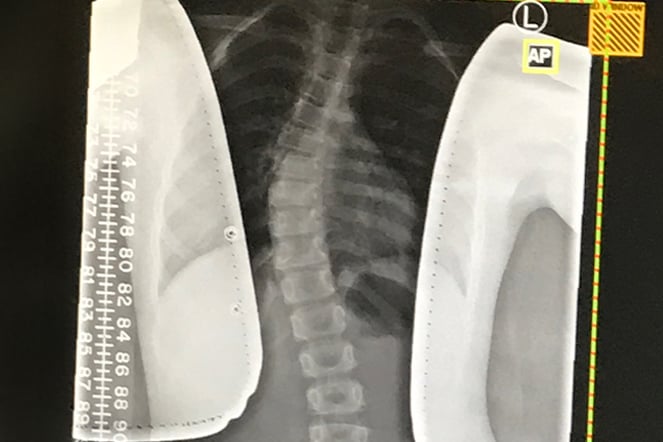

an x-ray of a spine with a curve

Lily's X-ray shows her scoliosis curve before bracing.

Lily is a patient at Shriners Children’s Philadelphia who was diagnosed with scoliosis, a curvature of the spine, when she was 5.

Our POPS department measures for customized braces that perfectly fit each child, and Lily has received several back braces as she’s grown over time as a patient at our hospital. As a result of Emily’s proactive care, Lily never had to undergo spinal surgery to correct her curve, as it improved solely through bracing. Lily has regular follow-up appointments with Dr. Pahys, who ensures her curve doesn’t progress.